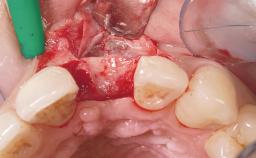

Immediate Placement of an Implant in a Maxillary Left Central Incisor Site

A 33-year-old female patient presented with an upper left central incisor that required extraction after a failed endodontic therapy. The tooth had been traumatized when the patient was a teenager and had undergone several endodontic treatments, including two apicectomy procedures. The patient was in good health and did not smoke. Clinical examination showed that the patient had a high lip line. In full smile, the gingival margins of the upper teeth were visible to the first molars. The gingival margins of central incisors 11 and 21 were only just showing. Examination of tooth 21 confirmed that the tooth was mobile and had hypererupted by 1 mm.

Placement Protocol Immediate implant placement

Socket Morphology Single-root socket

Socket Integrity Damage to one or more bone walls

Bone Volume Damage to one or more socket walls